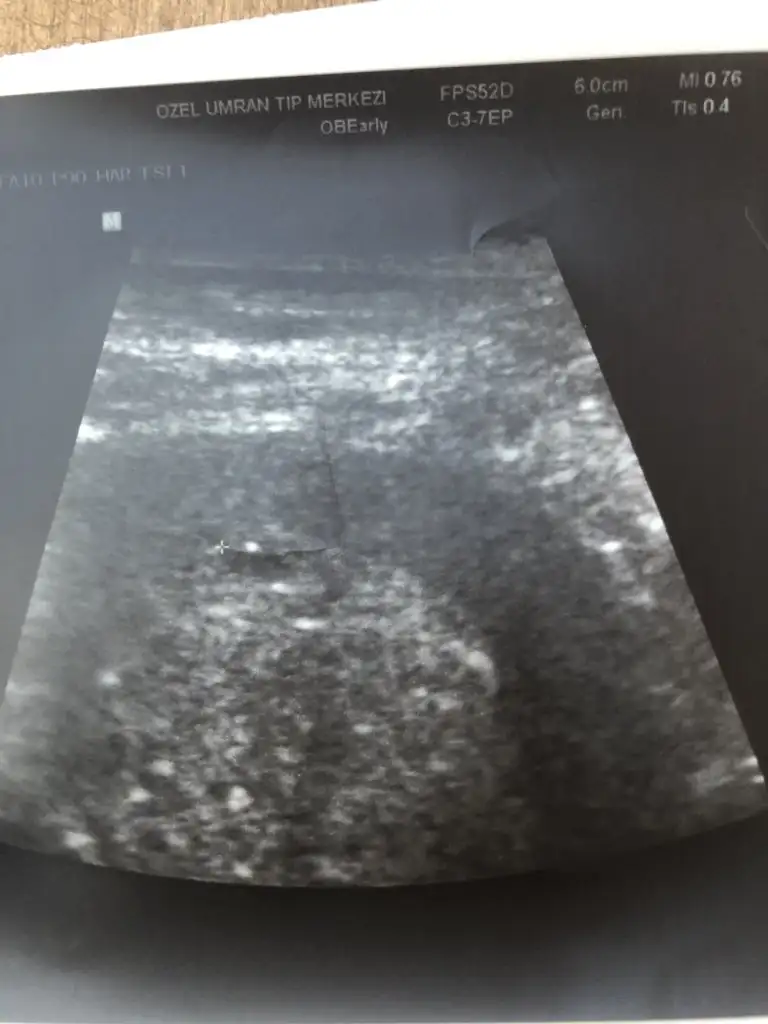

Kızlar kesemiz rahat gözüktü. Ama bebek konusunda öyle değil. Kese içinde beyaz bir şey var o bebek olabilir ama kesin değil dedi. Bebeğini gören arkadaşlarım var mı elinizde ultrason fotoğrafı?😇

Merhaba kızlar bugün 5+6 hafta bnm son adet tarihine göre. Keseyi gördük bugün haftaya da kalp atışı için çağırdı.

• A9DC4DD9-810D-40B4-8819-DFE2EF43CDE4.webp

A9DC4DD9-810D-40B4-8819-DFE2EF43CDE4.webp

22,7 KB · Görüntüleme: 79